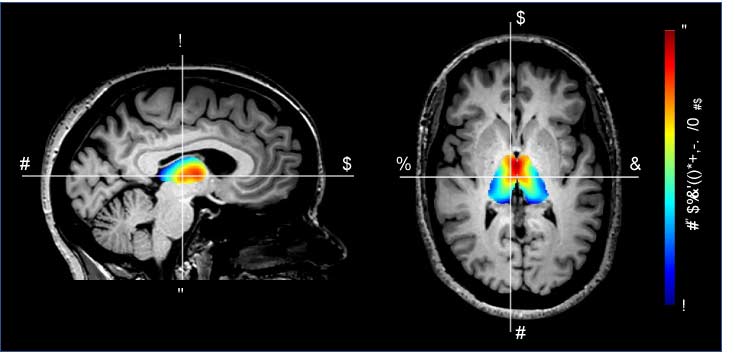

Neuroimaging and moral behavior

The Darby lab investigates the neural mechanisms underlying the most complex human behaviors at the interface of neurology, psychiatry, and philosophy, including moral behavior, delusions, and free will perception. Our lab’s overarching hypothesis is that these behaviors will not localize to a single brain region, but rather to common networks of connected brain regions that work together to bring about complex human behaviors. Our lab has worked to develop novel neuroimaging methods to test this network localization hypothesis in patients with focal brain lesions, dementia, and even psychiatric diseases. We also explore the ethical and legal implications of our research.